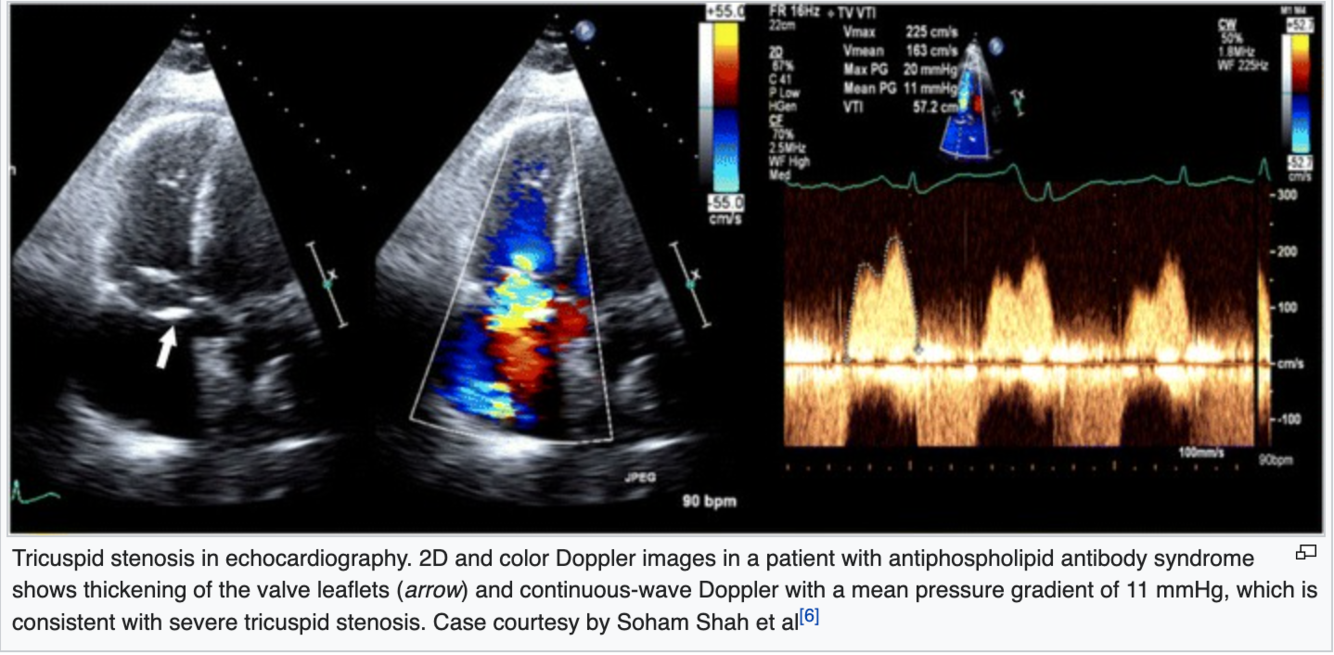

2D echo findings

A

• thickened TV leaflets with restricted motion

• diastolic doming of the TV leaflets best detected from the PLAX or 4C

• decreased TV orifice due to tethered leaflets

• RA enlargement due to volume and pressure overload

• dilated IVC (normal: 1.2-2.1cm) due to the backup of blood and RA enlargement

Quantification

views used to acquire sample volume?

• RV inflow

• PSAX

• A4C

• Subcostal SAX

*sample volume at tips of TV leaflets

Explain how to obtain pressure half time and TVA

• Compare PLAX RVIT, PSAX RVIT, A4C, A3C RVIT (modified view), Subcostal 4C/SAX if necessary

• Optimize Doppler angle

• CWD focus within the TV leaflets

• increase sweep speed to 100 mm/s

• Acquire the peak TS waveform, freeze, and measure from the peak velocity down to the deceleration slope *average 3+ waveforms

• The machine will calculate the P½t and TVA once the slope is acquired

TVA equation

TVA = 190/pressure half time

*190 is constant

20

Q

Tricuspid Stenosis

Explain how to obtain mean PG

• Trace the peak waveform, start and finish at ) baseline

• the machine will calculate the mean PG

21

severity scale: TVA

normal?

severe?

7-9 cm2

≤ 1.0 cm2

22

severity scale: P½t

≥190 m/s

23

severity scale: mean PG

≥ 5 mmHg